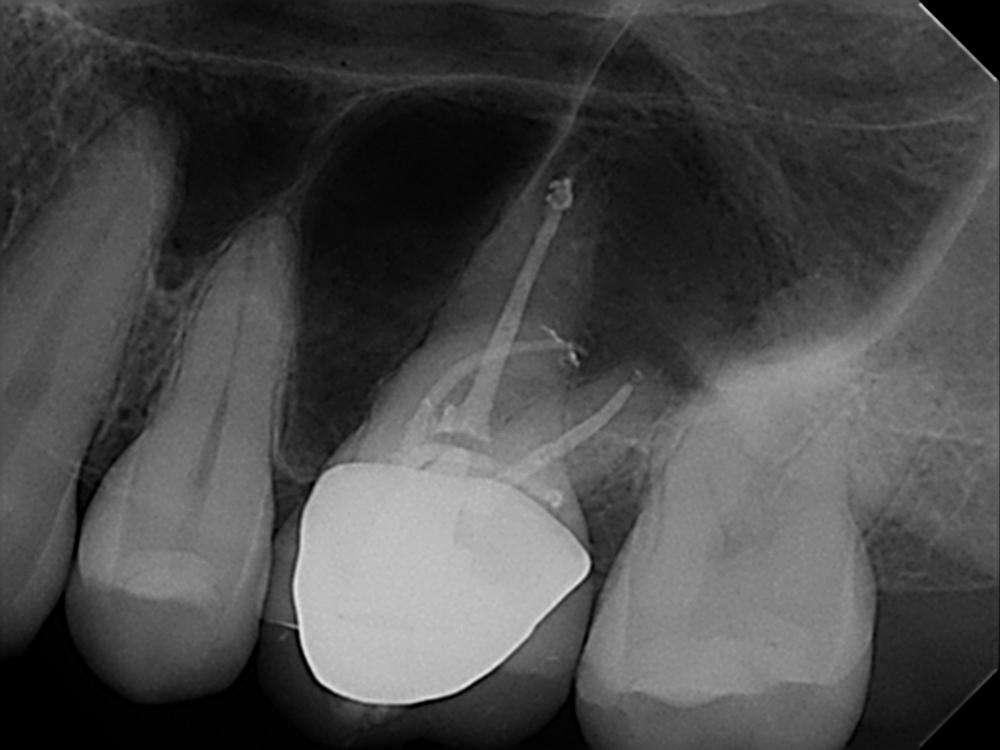

Röntgenologischer Befund:

Das präoperativ angefertigte Röntgenbild (Abbildung 10) zeigt den bereits vom Vorbehandler trepanierten Zahn 27. Die Wurzelfüllung erscheint inhomogen. Das Wurzelfüllmaterial im mesiobukkalen Kanal ist über den röntgenologischen Apex hinaus extendiert und es zeigt sich eine periapikale Osteolyse der mesiobukkalen Wurzel.

Abbildung 10: Präoperative diagnostische Aufnahme

Die Revisionsbehandlung erfolgte in zwei Sitzungen. Nach Anlegen des Kofferdams wurde die provisorische Füllung entfernt und die Zugangskavität gereinigt. Im Anschluss erfolgte die intrakoronale Diagnostik (Abbildung 11). Es zeigte sich bakteriell besiedeltes Wurzelfüllmaterial im mesiobukkalen, distobukkalen und palatinalen Kanal. Das Orifizium des mesiobukkalen Kanals war in palatinaler Richtung erweitert. Die Entfernung eines mesialen Dentinüberhangs mit langschaftigen Rosenbohrern legte das weit nach palatinal verlagerte Orifizium des zweiten mesiobukkalen Kanals frei. Die Entfernung des Wurzelfüllmaterials erfolgte mithilfe von EdgeFile X7 der Größe 25.06, und 17.06 in Crown Down Technik um die Verschleppung von Keimen und bakteriell besiedeltem Wurzelfüllmaterial nach apikal zu reduzieren. Die Erschließung und initiale Aufbereitung des zweiten mesiobukkalen Kanals wurde mithilfe der EdgeFile X7 der Größe 17.04, 17.06 in alternierender Weise wie oben beschrieben durchgeführt. Nach elektrometrischer Bestimmung der Arbeitslänge aller Kanäle wurde die Präparation mit EdgeFile X7 auf voller Arbeitslänge fortgesetzt. Im ersten mesiobukkalen Kanal, distobukkal und palatinal wurde die Aufbereitung mit EdgeFile X7 der Größe 40.06 abgeschlossen, während der zweite mesiobukkal Kanal bis 30.06 aufbereitet wurde (Abbildung 13).

Abbildung 11: Nach Ausarbeiten der primären Zugangskavität; Darstellung des mb2 in der Nähe des palatinalen Kanals

Nach Abschluss der Präparation wurden die Kanäle getrocknet, Kalziumhydroxid auf volle Arbeitslänge eingebracht und der Zahn provisorisch mit einer adhäsiven Kompositfüllung verschlossen. Die Weiterbehandlung fand nach zwei Wochen bei Beschwerdefreiheit statt. Nach erneuter elektrometrischer Kontrolle der Arbeitslänge, Anfertigung einer Masterpointaufnahme (Abbildung 12) und schallaktivierter Abschlussspülung mit 17% EDTA und 6% NaOCl wurden die Kanäle in warm vertikaler Fülltechnik mit biokeramischem Sealer gefüllt (Abbildung 15). Der direkte adhäsive Verschluss der Zugang erfolgte mit einem Bulk Fill Flow Komposit (Abbildung 14).

Abbildung 12: Masterpointaufnahme

Abbildung 13: Kanalsystem nach Aufbereitung

Abbildung 14: Nach Obturation und adhäsivem Verschluss Abbildung 15: Zugangskavität nach Obturation